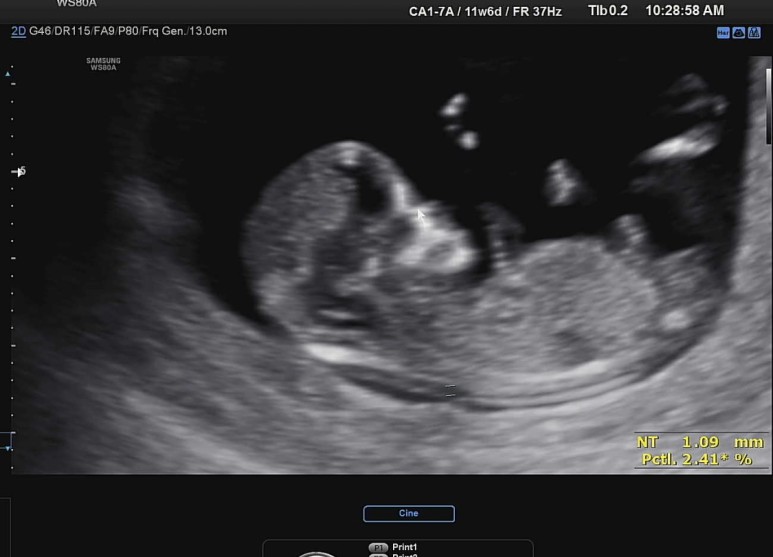

초음파가 시작되자마자 목덜미 투명대 부터 재 주시는..!

꿀잠이의 NT (목덜미 투명대 두께)는 1.09mm ! 아주 양호했다. 휴 :)

목덜미 투명대는 3mm 이상이면 다운증후군 고위험군에 속하고, 그렇게 되면 추가로 니프티 검사나 양수 검사를 산모의 선택에 따라 진행할 수 있는데, 니프티 검사는 어쨌거나 선별검사여서 저위험/고위험의 결과만 받을 수 있고, 양수검사는 확정검사이기 떄문에 다운증후군이 확정인지 아닌지 확실한 결과를 받을 수 있다.